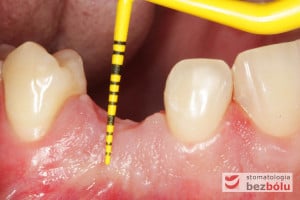

Procedurę chirurgiczną rozpoczęto od sprawdzenia przylegania szablonów do zębów pacjenta oraz znieczulenia miejscowego. W kolejnym kroku, przy pomocy specjalnie przeznaczonego do tego celu zestawu wierteł, wypreparowano krążki dziąsła punktowo odsłaniające kość a następnie poprzez tuleje prowadzące, z najwyższą precyzją, opracowano łoże implantu. Kulminacyjny moment zabiegu, czyli wprowadzenie wszczepów MIS C1 również odbyło się poprzez szablon, gwarantując precyzyjną lokalizację implantów. Zwieńczeniem całej procedury było przyszycie uprzednio wypreparowanych krążków śluzówkowo-okostnowych. Tuż po zabiegu, celem weryfikacji poprawnej pozycji implantów, wykonano zdjęcie ortopantomograficzne. Podczas wizyt kontrolnych, pacjent nie skarżył się na żadne dolegliwości bólowe, nie wystąpił obrzęk, a zreponowane we właściwych miejscach fragmenty dziąsła nie wykazywały oznak martwicy, co świadczyło o ich ponownym ukrwieniu i wgojeniu się. Wszystkie te przesłanki jasno wskazują na skuteczność zastosowania techniki komputerowej nawigacji w implantologii.